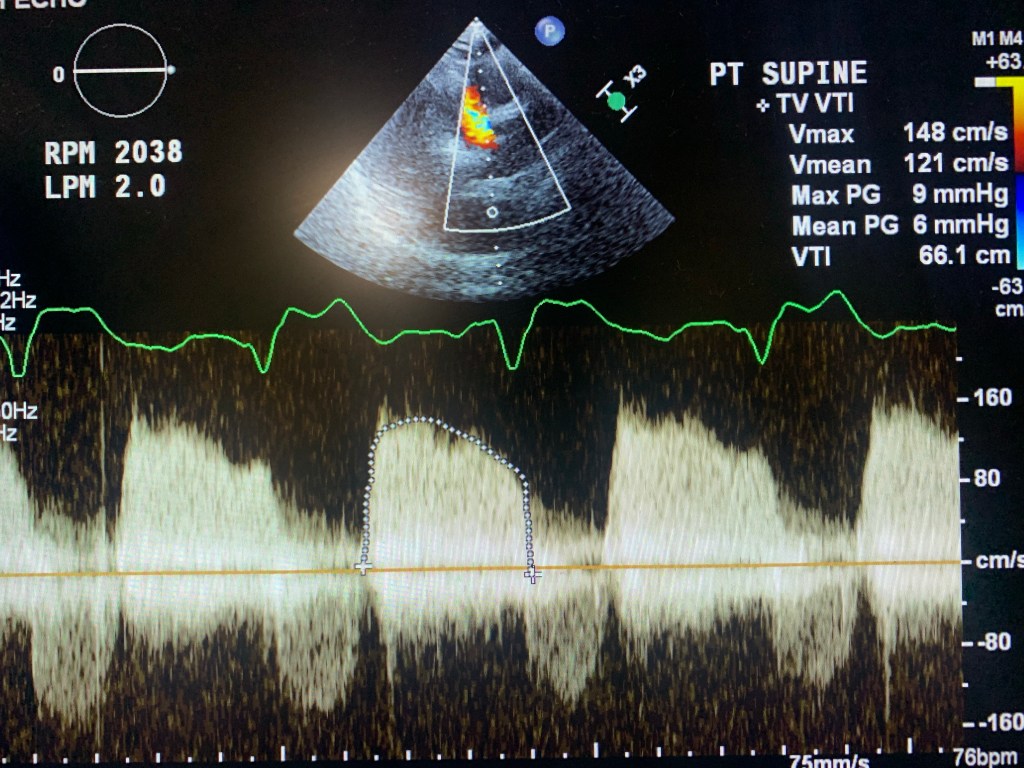

🔘 during RAMP studies: theres no LV dimention change with increased pump support/RPM

Below are a few images and videos of RVAD and changes in RAMP study I did recently